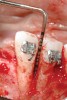

Figure 18   Implant placement with resulting facial dehiscence. Cortical perforations placed to promote angiogenesis.

Figure 18

Following the first goal of orthodontia—moving tooth No. 22 to a proper functional and anatomical position—a periodontal reevaluation was performed, demonstrating an improvement in short- and long-term tooth prognosis. At this time, the decision was made to abort continual extrusion of teeth Nos. 21 and 22, although some attachment level discrepancy remained between Nos. 21 and 22 (Figure 14). Implant diagnostics ensued and included mounted study models and a diagnostic wax-up. A scanning appliance was created to demonstrate the desired prosthetic outcome requirements, and the patient was referred for computed tomography (CT) scans. CT scan assessment demonstrated successful orthodontically directed GBR to allow implant placement (Figure 15 through Figure 16). Only minor GBR therapy would be needed and could be accomplished simultaneously with implant installation. Guided implant placement occurred, using an open flap approach (Figure 17). During surgery, root dehiscences were noted on teeth Nos. 21, 22, 24, and 25, as well as the anticipated dehiscence following implant placement at No. 23 (Figure 18). A positioning reference (index) was secured after implant placement to facilitate a provisional prosthesis at stage II surgery. Cortical perforations then were placed adjacent to the implant to encourage angiogenesis (Figure 18), and mineralized freeze-dried bone allograft enhanced with platelet-derived growth factor was placed over the dehiscences for purposes of guided tissue regeneration and GPR (Figure 19). A highly resorbable collagen membrane was placed to stabilize the allograft. The flap was coronally repositioned, and primary-intention wound healing was achieved (Figure 20 and Figure 21). Following 4 months of stage I surgery, implant uncovery and immediate provisionalization was performed in conjunction with connective tissue grafting. Final orthodontic tooth movement then ensued, using the implant as anchorage to optimize end-tooth movements, interroot separation, and the cuspid-protected occlusal scheme. A final impression then was secured, and a zirconia abutment (Figure 22) with an all-ceramic restoration was fabricated for the prosthetic phase completion of No. 23 (Figure 23] through Figure 25).